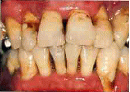

なぜ歯周病になるのでしょうか?歯周病も虫歯と同じ感染症です。

歯周病は特殊な細菌により引き起こされています。その細菌を媒介するのがプラーク(歯垢)です。ですから歯の周りにこのプラークが付いていないこと、あるいは歯石がついていないことが歯周病を起こさないためには重要です。

プラークは歯ブラシで落とすことが出来ますが、歯石は石のように硬く、また歯や根にしっかりとこびりついている為、歯ブラシでは落とすことができません。そのため、歯石を取るためには特殊な器具、装置が必要です。

この歯周病を予防するために当院ではPMTCを行っています。